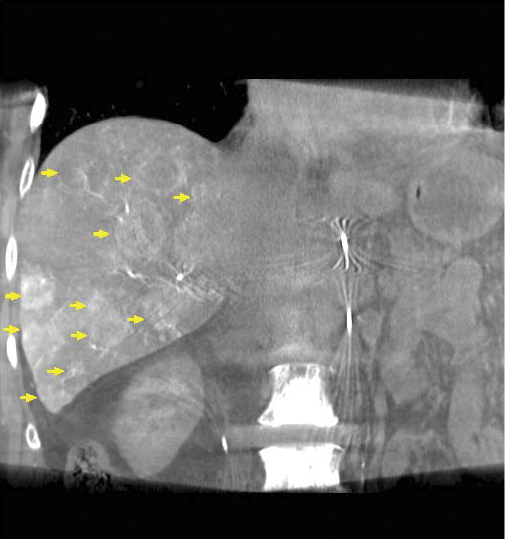

New research on the minimally invasive, image-guided therapy Yttrium-90 (Y-90) radioembolization shows promise in treating breast cancer that has spread to the liver when no other treatment options remain.

In research presented at the 2014 Society of Interventional Radiology Annual Meeting, Dr. Lewandowski and colleagues treated 75 women (ages 26-82) with breast cancer liver metastases, all of whom had progressive disease. In addition, 85 percent of these women had multiple liver tumors and 77 percent had disease outside the liver.

Researchers determined that the tumors got smaller or remained stable in 98.5 percent of the patients after radioembolization, while tumor reduction of more than 30 percent occurred in 24 patients. Additionally, these women experienced no major side effects.

In Y-90 radioembolization, an interventional radiologist guides a catheter into the hepatic artery that supplies blood to the liver. Microbeads containing radioactive Y-90 are then injected and float downstream to deliver cancer-killing radiation inside the heart of the tumor.